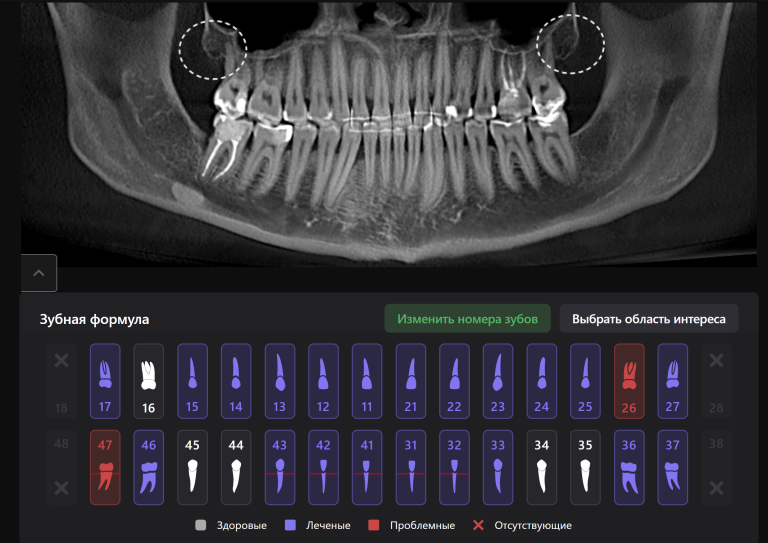

Для принятия клинического решения врач проанализировал данные осмотра и рентгенологического отчета Diagnocat. В отчете содержится оценка ранее проведенного лечения и данные о наличие признаков периапикальных изменений

Обратите внимание на высокий процент вероятности, который предлагает Diagnocat. Принято решение о сохранении зубов и проведении повторного эндодонтического лечения